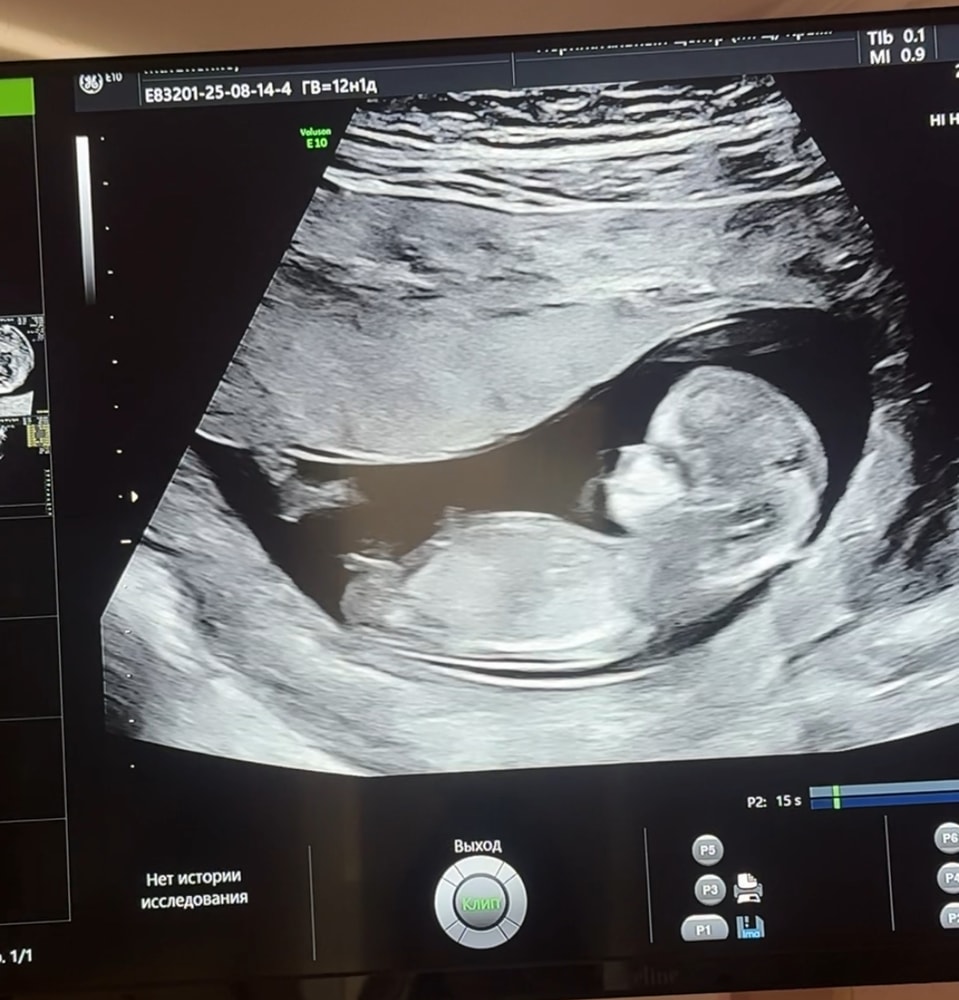

Есть предположения? :)

Анализы, скринингиДевочки, была на 1 скрининге , узист пол не сказала , а я сгораю от интереса 😅 может на опыте кто-то понимает 😂

Девочка по инфе с инета. У мальчиков полов бугорок вертикально вверх, а тут параллельно позвонку

Мне кажется, девочка ☺️ Хотя бугорок не в явном положении, вполне и мальчиком может оказаться.